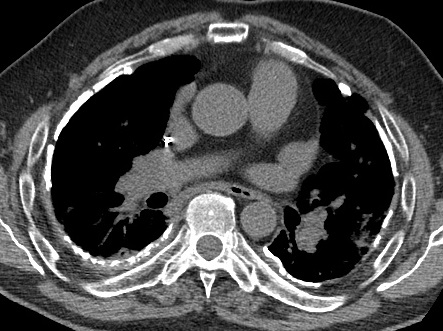

Image

radiolologique cliche de face PA d'une epaissisement

pleural diffuse du poumon droit par consequence de

tuberculose du poumon droit . Aspect radiologique

est opacite en plaque de tres densite s'étend et

recouvre tout le poumon droit , Poumon droit en

fibrose restrictive |